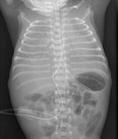

(1)胃鏡檢查 有特殊重要性,早期在胃的近段黏膜上可見多數散在的蒼白斑點,24~36小時后即可見多發性淺表紅色的糜爛點,以后即可出現潰瘍,甚至呈黑色,有的表現為活動性出血。